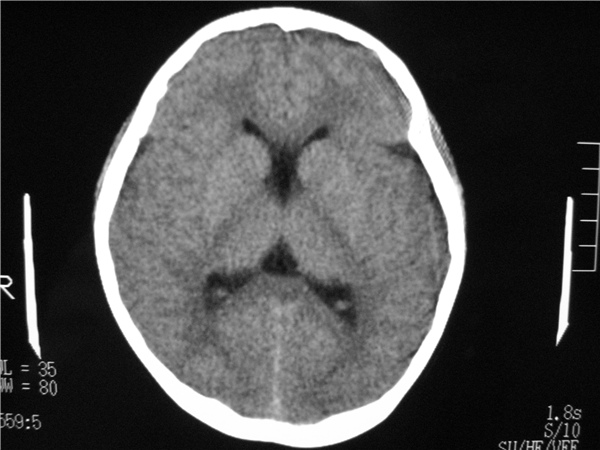

以下是引用随光逐影在2009-8-1 14:17:00的发言:[br]透明隔囊肿与vergae腔并存。

以下是引用zjzjr在2009-8-1 14:51:00的发言:[br]五、六脑室形成。